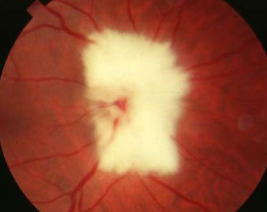

MNF

myelinated retinal nerve fiber (MRNF)

congenital

incidence: 0.3-1%

males = females

oligodendrocytes sheath axons

bilateral in 8% of cases

contiguous w/ ONH in 33% of cases

associations:

myopia

strabismus

amblyopia

appearance:

retinal dense white opacification w/ soft feathered or frayed edges, fine striations following RNF, tend to fan out

isolated patches seen away from ONH in mid-periphery

size varies from ½ DD to several DDs

complications:

rarely macula is involved, but if so, decreased VA)

relative VF defect

must r/o CWS, retinal ischemia, or pale disc

papilledema is partially translucent grayish-white appearance of true edema compared to MNF w/ denser white w/ feathered edge & obscures vessels at disc margin

how do you differentiate between papilledema & MNF?